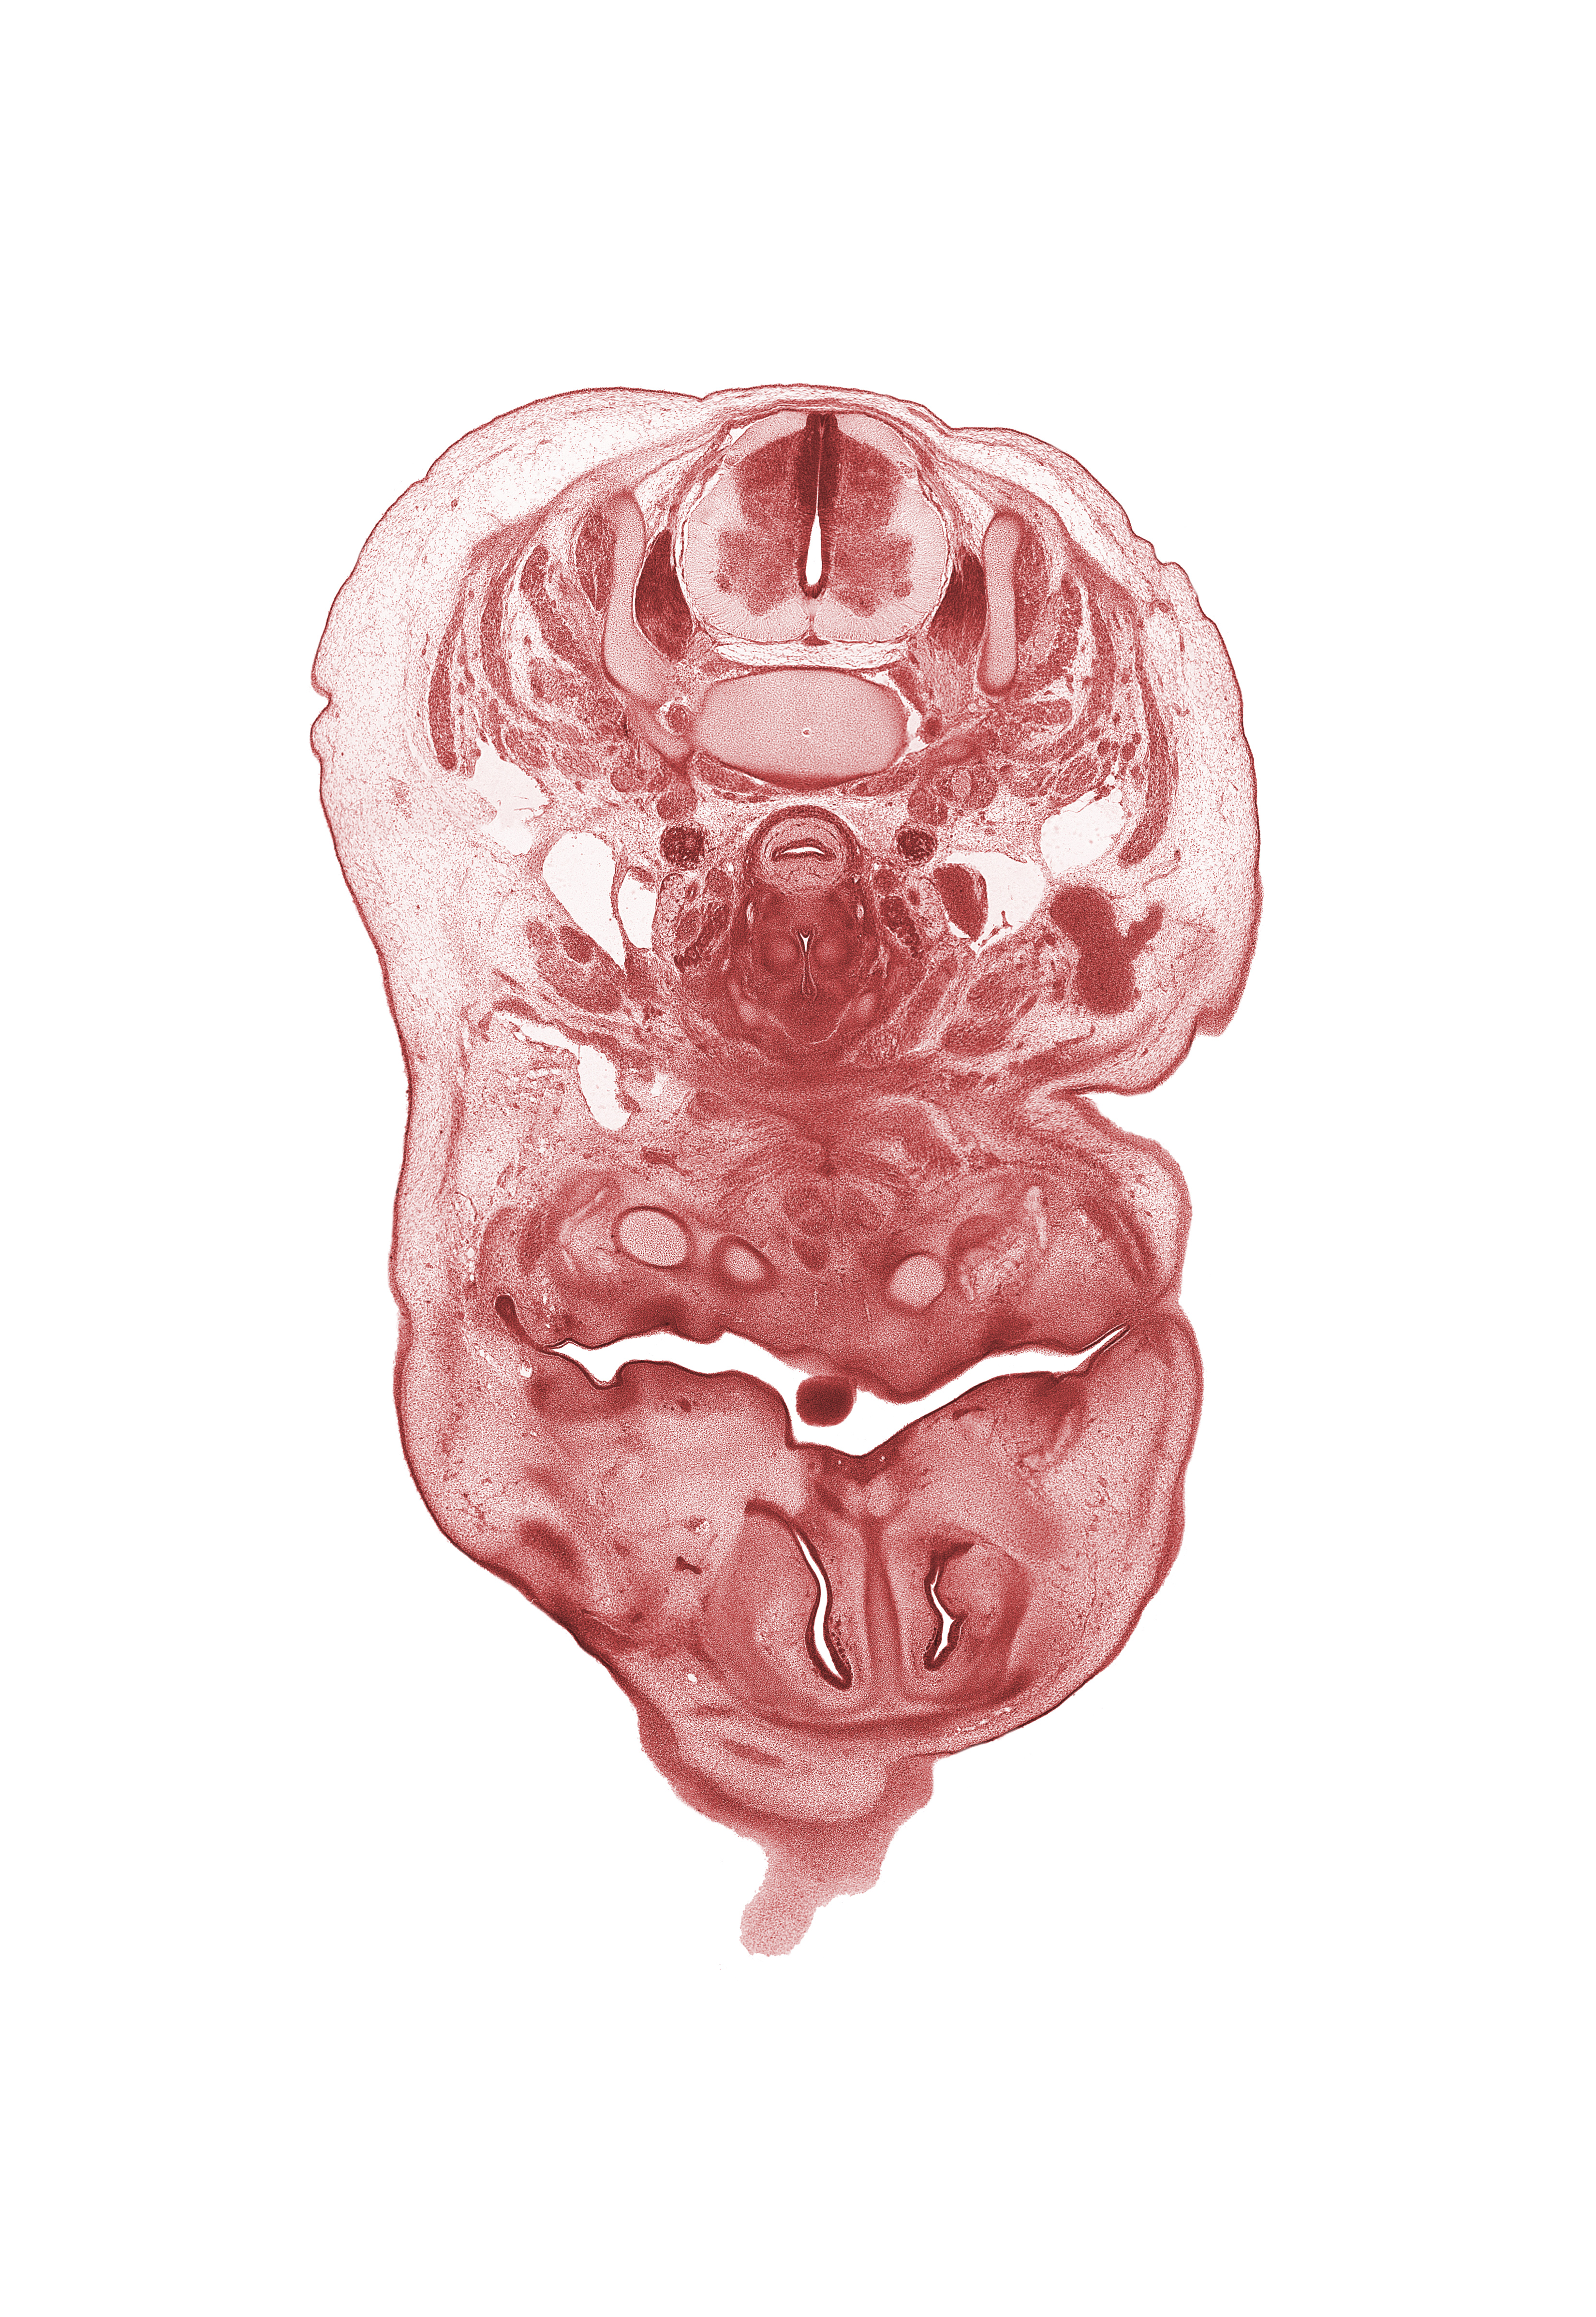

0 μm

Carnegie Embryo #462 | Location: 3-04-03

Keywords: C-5 spinal ganglion, C-5 spinal nerve, blastema of facial muscle, buccal region, edge of frontal prominence, esophagus lumen, external jugular vein, internal carotid artery, internal jugular vein, interorbital ligament, neural arch, oral cavity, pharyngeal arch 1 cartilage (Meckel), platysma muscle, retro-esophageal space, superior parathyroid gland, tip of tongue, trapezius muscle, vertebral artery

Source: The Virtual Human Embryo.